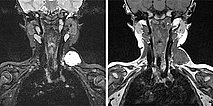

In der koronaren MRT (linkes Bild: T2-Wichtung, rechtes Bild: T1-Wichtung nativ) ist die venöse Malformation sehr gut abgrenzbar. In der T2-Wichtung ist sie stark hyperintens, in der nativen T1-Wichtung isointens zur Muskulatur. Die Signalgebung ist klassisch für den Charakter einer Slow-flow-Läsion.

In der koronaren MRT (linkes Bild: T2-Wichtung, rechtes Bild: T1-Wichtung nativ) etwas weiter dorsal, ist sehr gut ein größerer Thrombus innerhalb der venösen Malformation abgrenzbar. In der T2-Wichtung ist dieser hypointens im Vergleich zur stark hyperintensen VM. In der nativen T1-Wichtung ist er ganz gering hyperintenser als die umgebende hypointense VM.